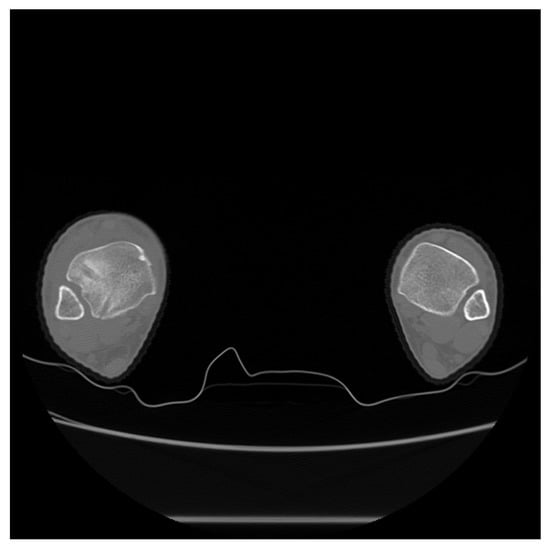

2. Case Presentation